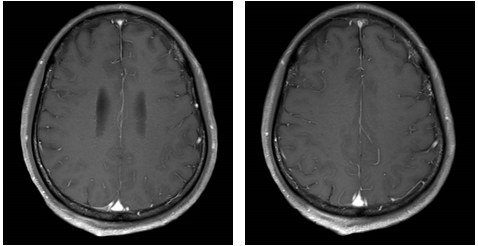

免疫联合化疗(2022年12月):紫杉醇+卡铂+PD-1抑制剂+贝伐珠单抗,共6周期。治疗后积液显著吸收,脑转移灶缩小。

维持治疗及随访(2023年6月至今):紫杉醇+PD-1抑制剂+贝伐珠单抗维持治疗。2025年6月MRD检测发现SMARCA4突变低丰度阳性,提示可能复发,需进一步评估。

新加坡国家癌症中心Kevin Lee Min Chua教授:在分析患者治疗情况时,我们发现其接受的系统治疗虽全面,但疾病控制效果短暂,每6个月随访便显示病情进展。同时,患者对紫杉醇+PD-1抑制剂+贝伐珠单抗维持治疗缓解不佳,这促使我们思考后续治疗策略。MRD检测揭示复发风险,却未明确复发位置。此时,借助PET-CT或脑部MRI检查,或许能定位潜在复发病灶。

中山大学肿瘤防治中心陈宝清教授:在分析脑转移病例时,关键在于患者是否已接受或考虑过放疗。在我们的临床实践中,针对脑转移,是否放疗取决于患者具体情况。若脑转移范围有限且其他病灶控制良好,放疗通常是重要选择。因此,我认为放疗在此案例中可作为优先选项。